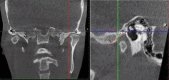

The success of complex prosthodontic treatment is believed to be conditioned by condylar path replication in the articulator, as there is a continuing debate in the scientific community regarding the anatomical relationship between joint and dental morphology. The purpose of this study was to investigate the potential correlation between incisal and condylar guidance. The study population consisted of 20-30-year-old full dentate individuals with Angle class 1 occlusion, whose cone-beam computed tomography (CBCT) scans were analyzed by two investigators. The anterior slope of the right and left glenoid fossa angle and the palatal slope of all maxillary frontal teeth were measured by software tools at three defined landmarks, and the mean values were calculated. Statistical analysis was performed using IBM SPSS Statistics software (version 19.0), and the Pearson r coefficient test was used to assess correlations. The results reveal a highly statistically significant correlation between median condylar slopes and between median incisal slopes of the anterior teeth, on the left and right side, in the three standard areas (p<0.01). However, no significant correlation was found between the condylar slopes and the incisal slopes of the anterior teeth (p>0.01) in class 1 Angle subjects. In conclusion, this study did not provide evidence to support the existence of a significant correlation between incisal and condylar guidance in the population under investigation.